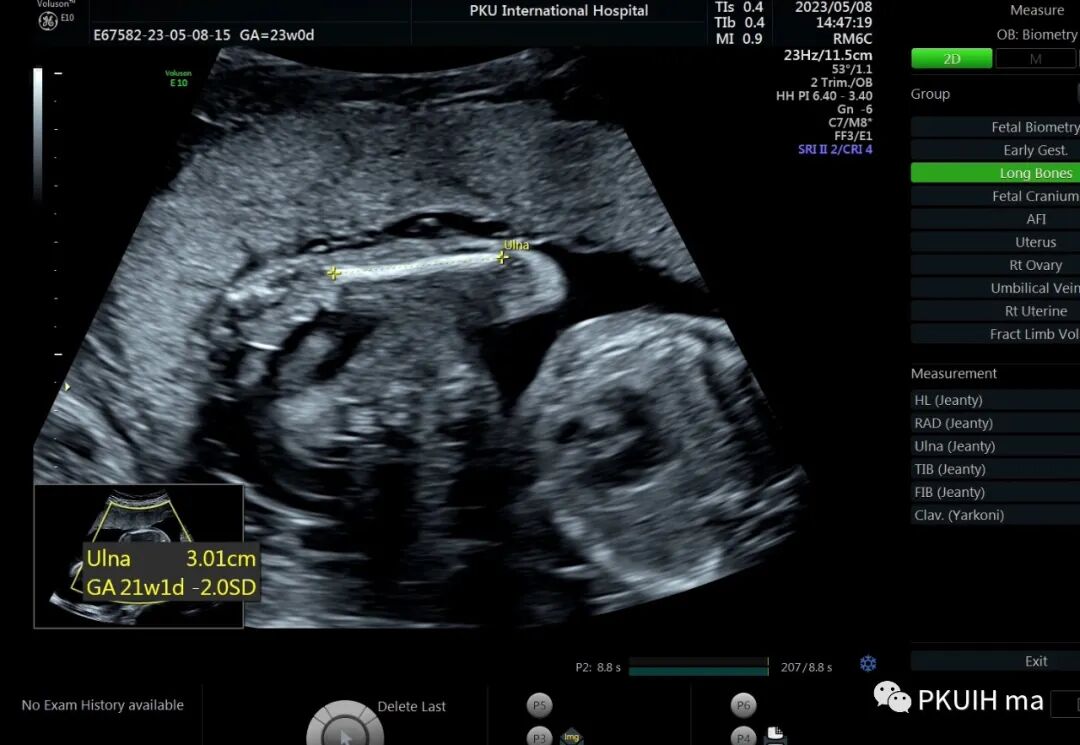

孕23周常规筛畸发现四肢长骨偏短,孕妇月经正常,核对早孕超声,孕周也没问题。

双顶径及头围正常,骨骼回声强度没有发现异常。